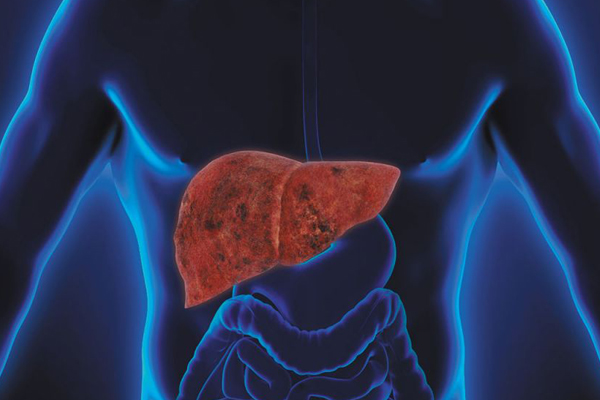

Gastrointestinal disorders

Cancer